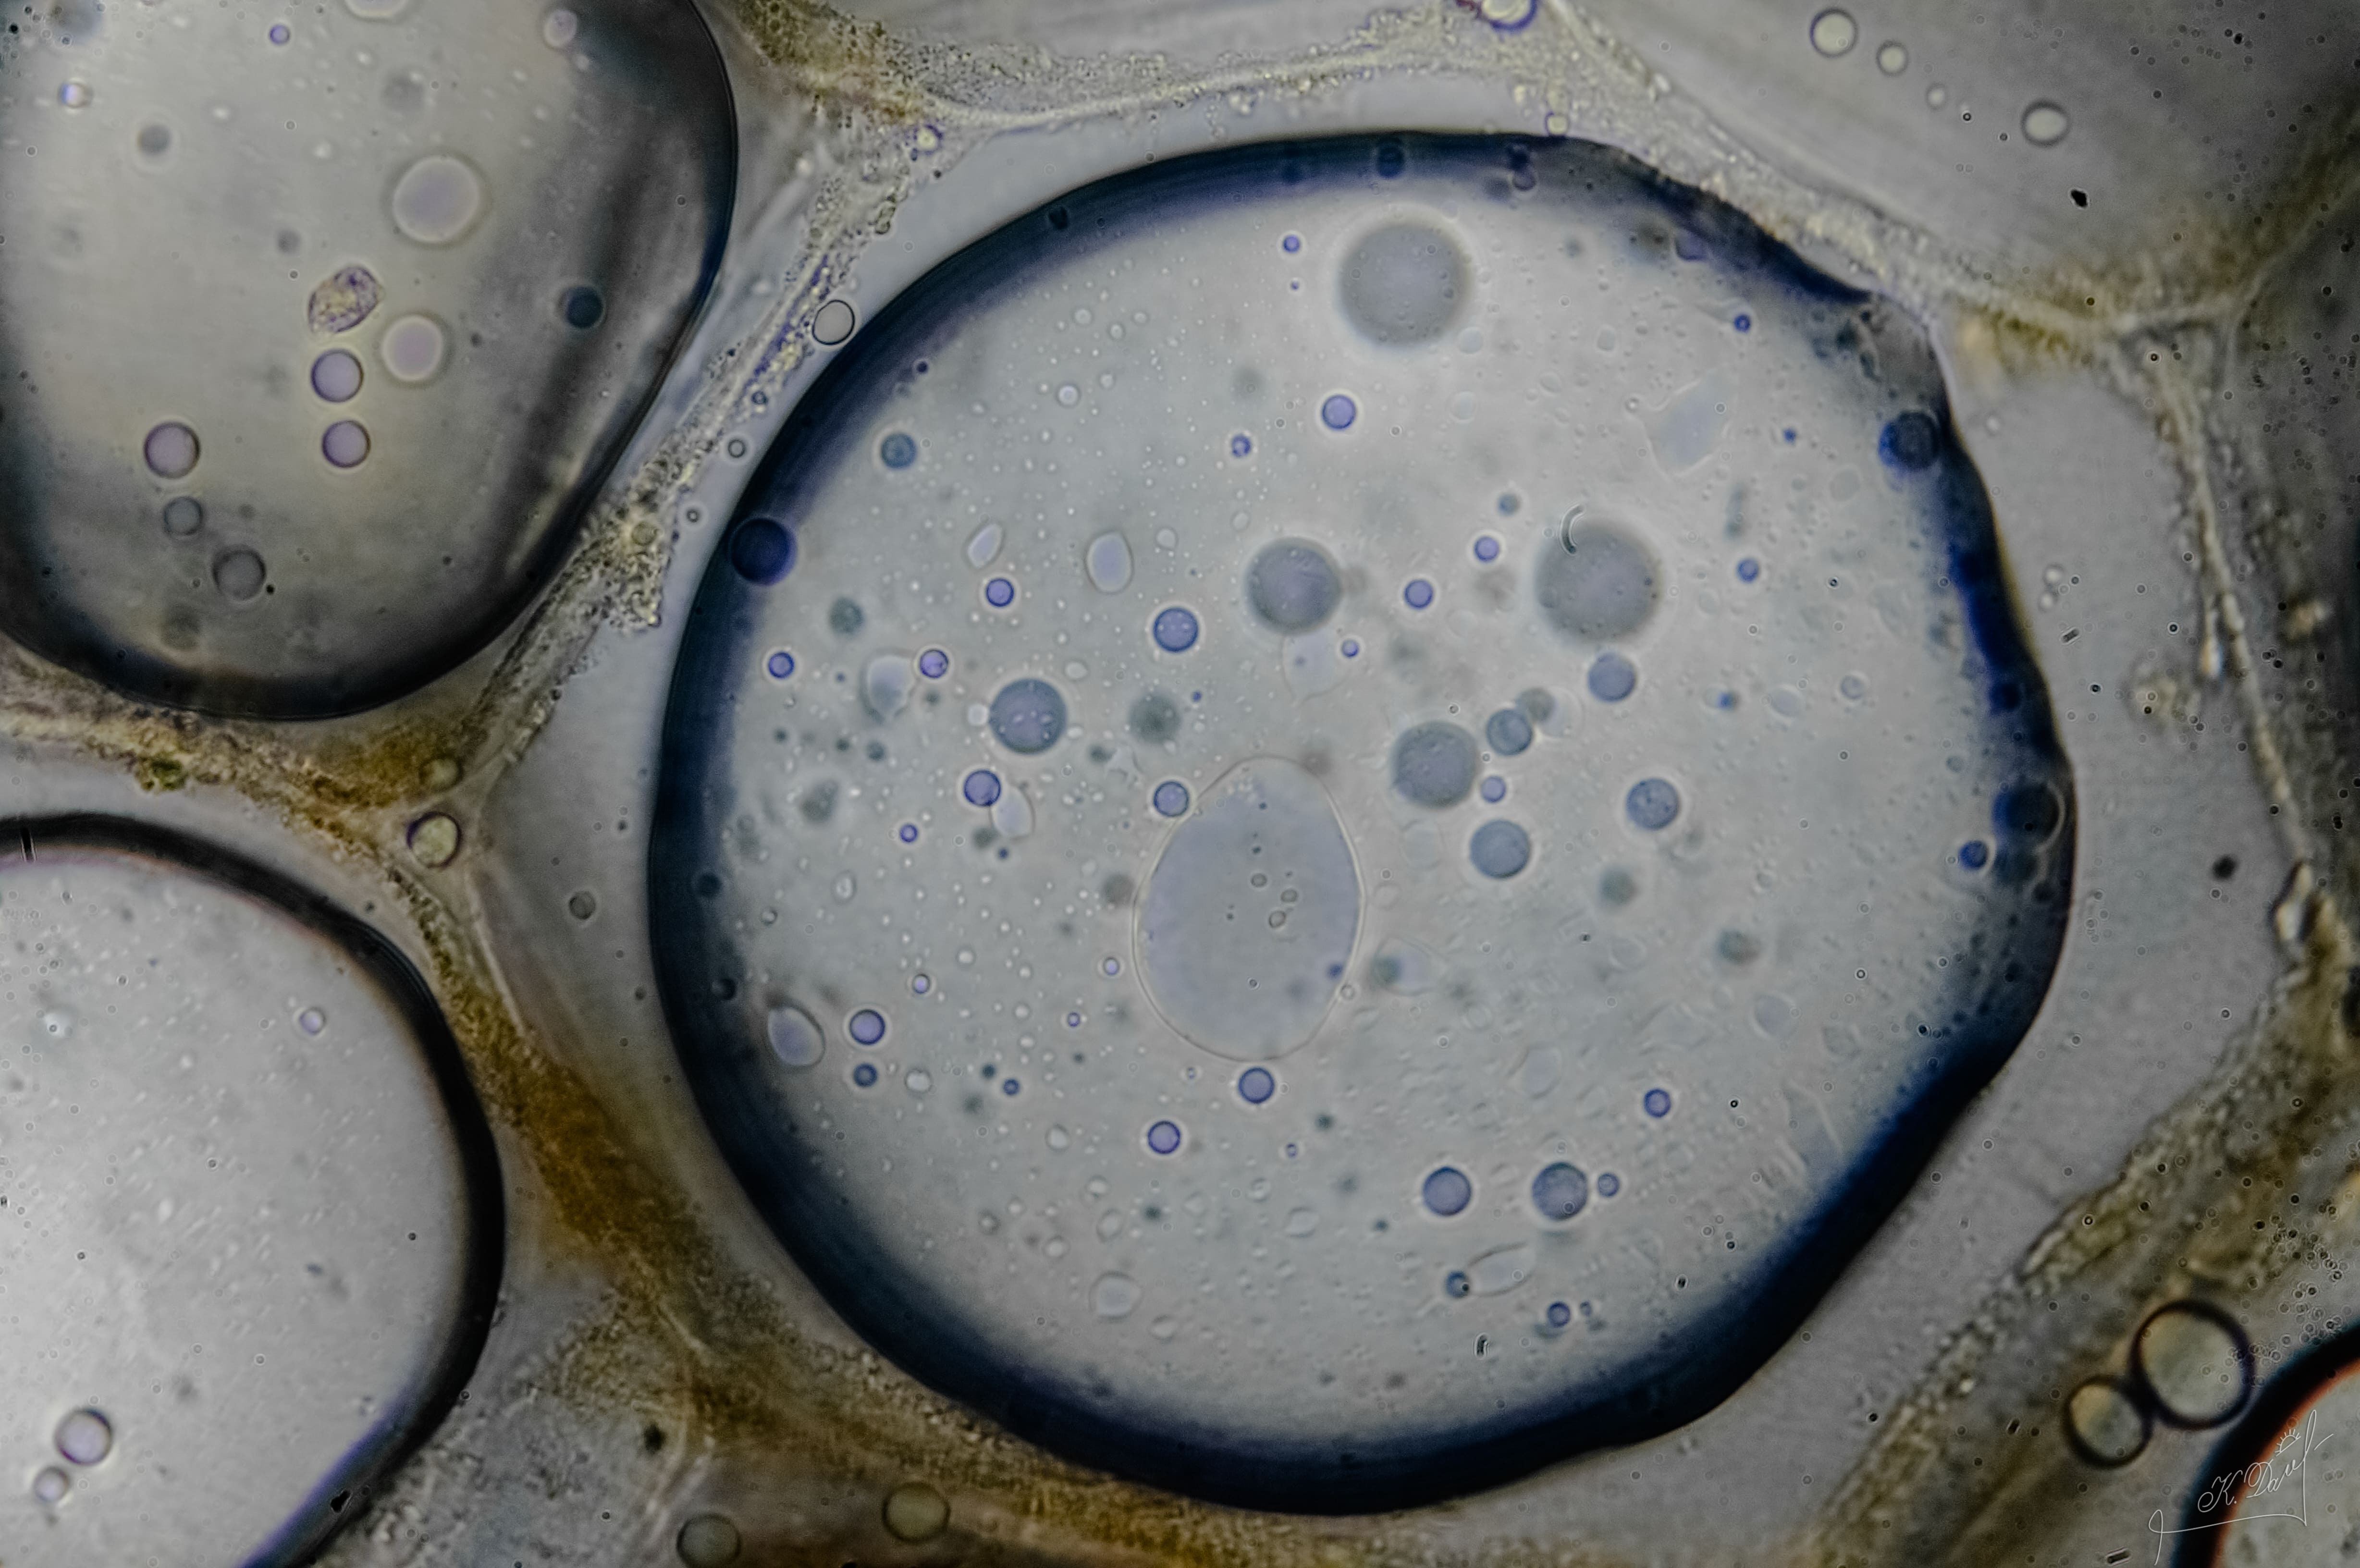

Как заявил уролог-андролог, перегрев органов репродукции у мужчин приводит к снижению выработки жизнеспособных сперматозоидов. Температура половых органов у мужчин должна быть на пару градусов ниже тела.

Неправильное ношение термобелья создает эффект «сауны», что снижает подвижность сперматозоидов. Теплая и влажная среда в области половых органов повышает риск размножения бактерий и грибков.

Фото: commons.wikimedia.org, Кузнецов Денис Аркадьевич, Creative Commons Attribution-Share Alike 4.0 International license.